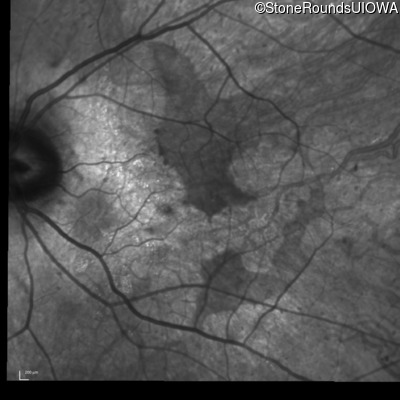

Infrared Fundus Photograph - Left - 20/40 sc

Exemplar